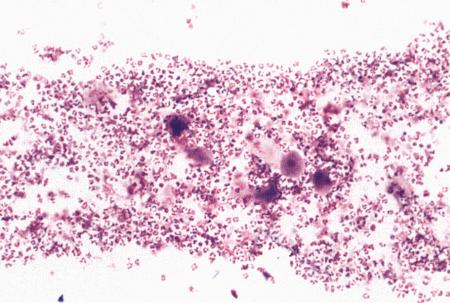

Вагинальная цитология

Повышение концентрации эстрадиола в период проэструса стимулирует деление клеток в базальных слоях вагинального эпителия, но затем концентрация эстрадиола, а соответственно и эндокринная поддержка образования нового, многослойного эпителия снижается, поэтому в образце обнаруживается больше мертвых ороговевших клеток. По мере развития проэструса снижается количество эпителиальных клеток, содержащих ядро. С начала до середины проэструса в вагинальных мазках обнаруживают повышенное содержание эритроцитов. Пик ороговения совпадает с началом повышения концентрации прогестерона; однако в начале эструса исследование не обнаруживает характерных особенностей, которые могли бы указывать на начало фертильного периода. Как правило, такой период наступает несколькими днями позже (табл. 1.1). Тем не менее вагинальная цитология остается популярным методом определения репродуктивного статуса суки из-за своей дешевизны, простоты и доступности. Для получения образца используют ватный тампон, предпочтительно небольшой, который вводят во влагалище и осторожно берут мазок. Полученные клетки помещают под микроскоп, а затем окрашивают контрастным (трихромом) или неконтрастным (например, препаратом Diff-Quik) веществом. При таком окрашивании мертвые кератинизированные клетки становятся оранжевыми, тогда как активные ядерные клетки, а также базальные и парабазальные эпителиальные клетки приобретают различные оттенки от голубого до зеленого.

Ближе к окончанию эструса вагинальные выделения претерпевают характерные изменения (снова выявляются эпителиальные клетки, содержащие ядро, и появляется большое количество лейкоцитов). Такая картина обычно наблюдается через 7–9 дней после пика ЛГ и известна как «вагинальный мазок метэструса». Изменению характера выделений предшествует переходный период, характеризующийся возрастающим количеством активных клеток и указывающий на окончание фертильного периода и эструса (табл. 1.1).

Вагинальная цитология весьма информативна в плане определения фазы эстрального цикла, однако значительные расхождения во времени появления основных признаков эструса по отношению к пику фертильности ограничивает применение указанной методики.

Фиг. 2.2.

Вагинальные выделения кошки (а). Выделения, типичные для фазы эструса. Большая часть клеток представляет собой безъядерные кератинизированные клетки или клетки с пикнотическим ядром. Присутствуют промежуточные клетки (b). Выделения, характерные для метэструса, — «течки», иногда наблюдаемой у кошек в конце эструса. Присутствуют поверхностные и промежуточные клетки, повышено содержание лейкоцитов. Этот короткий метэструс наблюдается в течение 24–48 часов (см. Приложение)